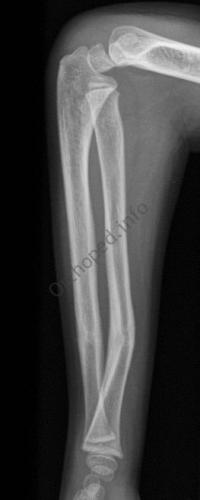

Fracture de l’avant-bras 31 mars 202519 mars 2024 par Damien Traitement Traitement orthopédique Embrochage centro-médullaire